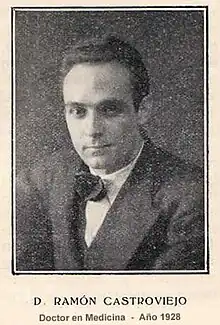

The first cornea transplant was performed in 1905 by Eduard Zirm (Olomouc Eye Clinic, now Czech Republic), making it one of the first types of transplant surgery successfully performed. Another pioneer of the operation was Ramón Castroviejo. Russian eye surgeon Vladimir Filatov's attempts at transplanting cornea started with the first try in 1912 and were continued, gradually improving until on 6 May 1931 he successfully grafted a patient using corneal tissue from a deceased person.[26] He widely reported another transplant in 1936, disclosing his technique in full detail.[27] In 1936, Castroviejo did a first transplantation in an advanced case of keratoconus, achieving significant improvement in patient's vision.[28][29]